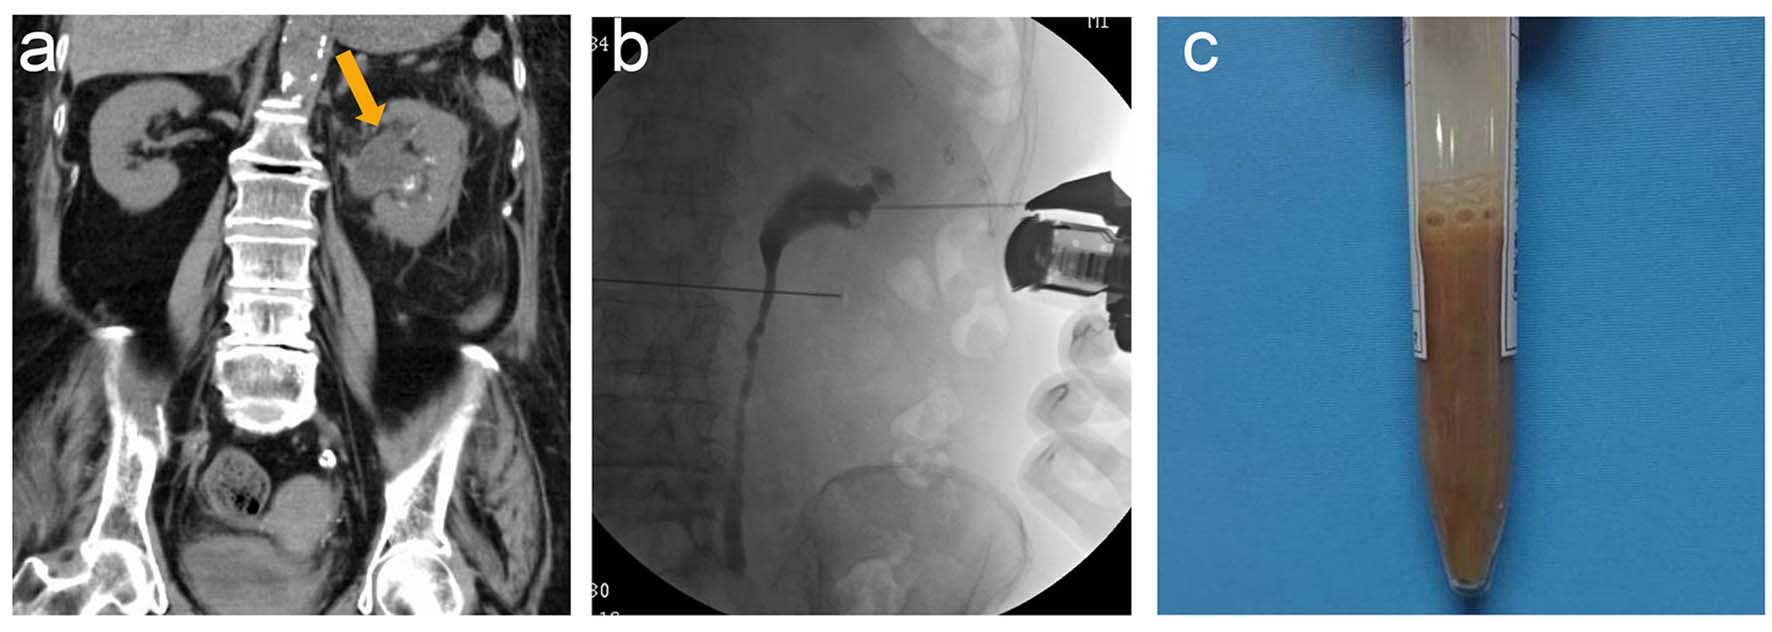

An 87-year-old female visited our hospital with a high-grade fever, nausea, and diarrhea. Her past medical history included cerebral dementia, type 2 diabetes mellitus, and dyslipidemia. The physical examination upon her arrival revealed that her blood pressure was 100/72 mm Hg, heart rate was 100 beats/min with a regular rhythm, blood oxygen saturation was 97% under atmospheric conditions, and her body temperature was 39.5 °C. Moreover, she exhibited a disturbed consciousness disturbance with a II-30 score of the Japan coma scale (JCS). The blood analysis revealed a reduced number of white blood cells (WBCs 2,110 cells/μL), mild hypoproteinemia (6.7 g/dL), severe hypoalbuminemia (2.5 g/dL), and impaired glucose tolerance (208 mg/dL glucose and 7.6% hemoglobin A1c). The urinalysis revealed more than 100 WBCs/HPF, 30 - 49/HPF red blood cells (RBCs), as well as severe proteinuria. Non-contrast computed tomography (CT) revealed a dilated left ureter, swollen left kidney with fat stranding in the retroperitoneal space, and an incarcerated stone in the upper left ureter (Fig. 1a). The patient was diagnosed with infective hydronephrosis, and was subsequently admitted to our hospital for further examination and treatment. The administration of flomoxef sodium at a dose of 2 g/day was initiated. The high-grade fever continued, and then her serum platelet levels dropped from 12.6 × 104 to 11.2 × 104 cells/μL on the following day. On day 3, the high-grade fever continued and the laboratory analyses revealed remarkably elevated C-reactive protein levels (28.92 mg/dL), drastically elevated procalcitonin levels (> 100 ng/mL), further reduced platelet levels (9.7 × 104 cells/μL), and deteriorated renal function (creatinine levels 1.14 mg/dL; blood urea nitrogen 23.6 mg/dL). Moreover, the urine and blood culture obtained upon admission was positive for Escherichia coli. At this time, abscess drainage of the left pelvis was scheduled to control the infection and a percutaneous nephrostomy (PCN) tube was inserted (Fig. 1b). The drainage contained brown pus with a foul odor (Fig. 1c). The drainage culture revealed positive results for E. coli, which was sensitive to cefmetazole (CMZ). The antibiotic drug was changed to CMZ at a dose of 3 g/day. On day 6, the WBC count dropped to 3,420 cells/μL, fibrin degradation products (FDP) were elevated to 45 μg/mL, and the platelet count was 8.1 × 104 cells/μL, which was consistent with a DIC score of four points. An administration of 12,800 IU rhTM was initiated and continued for 3 days until the DIC score dropped to three points. Moreover, there was an improvement in the inflammatory reaction, platelet levels, and coagulant disturbance. The clinical course was shown in Figure 2.

![]() Click for large image | Figure 1. (a) Non-contrast computed tomography revealed a dilated left ureter and swollen left kidney with fat stranding in the peritoneal space. (b) A percutaneous nephrostomy tube was inserted under ultrasonography, revealing a dilated ureter and renal pelvis. (c) The drainage contained brown pus with a foul odor. |